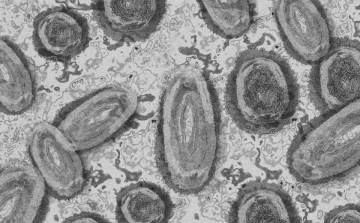

Tovább nőtt a majomhimlő-fertőzöttek száma Magyarországon

Újabb két embernél igazolt majomhimlő-fertőzést a Nemzeti Népegészségügyi Központ (NNK) a 33. héten - augusztus 15-től 21-ig -, ezzel 64-re nőtt a magyarországi esetek száma.

Meghaladta a 13 ezret a majomhimlő-fertőzöttek száma az Egyesült Államokban

Meghaladta a 13 ezret a majomhimlő-fertőzöttek száma az Egyesült Államokban, a legtöbb esetet Kaliforniában és New York államban regisztrálták.

Megfertőződött a majomhimlővel egy gyerek Németországban

Megfertőződött majomhimlővel egy négyéves kislány Németországban - jelentették kedden német hírportálok az országos közegészségügyi intézet (RKI) adatai alapján.

Újabb kilenc, 23-50 éves férfinél igazolták a majomhimlő-fertőzést Magyarországon, ezzel 42-re nőtt a fertőzöttek száma - közölte a Nemzeti Népegészségügyi Központ (NNK) csütörtökön az MTI-vel.

Tovább nőtt a majomhimlő magyar fertőzöttjeinek száma

Újabb hat embernél diagnosztizálták a majomhimlő vírusát, így harmincra emelkedett az igazolt fertőzöttek száma Magyarországon - közölte a Nemzeti Népegészségügyi Központ (NNK) pénteken az MTI-vel.